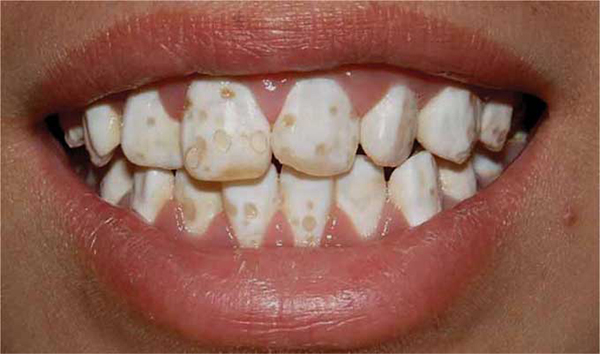

Фото эрозивной, эндемической, штриховой формы

Фото 2. Эндемическая форма флюороза, равивается по причине повышенного содержания фтора в питьевой воде.